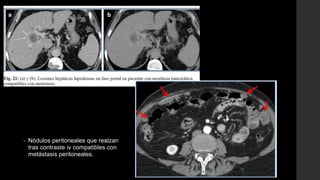

• Nódulos peritoneales que realzan

tras contraste iv compatibles con

metástasis peritoneales.

• Nódulos peritonealesque realzan tras contraste iv compatibles con metástasis peritoneales.